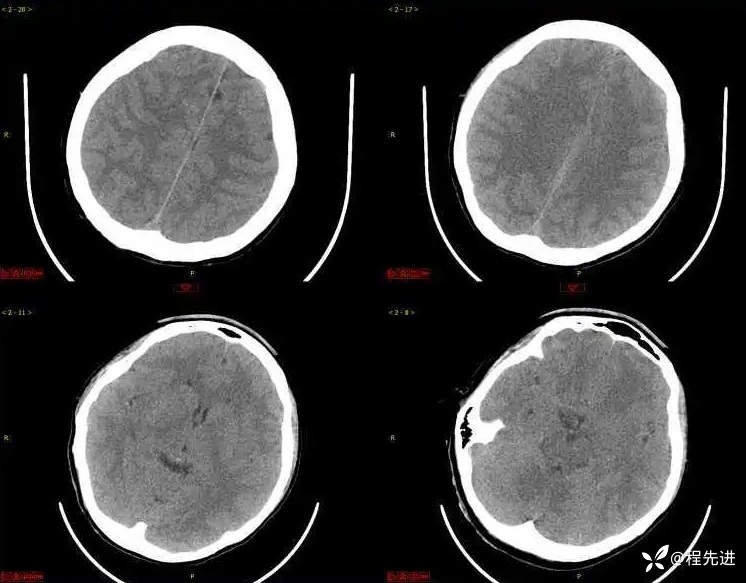

CT平扫: